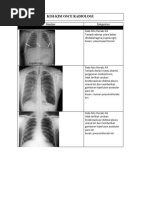

Beberapa dokumen menunjukkan hasil pemeriksaan yang normal, sementara yang lain menunjukkan berbagai kondisi medis seperti fraktur, pneumonia, osteoporosis, dan kelainan pada organ dalam.